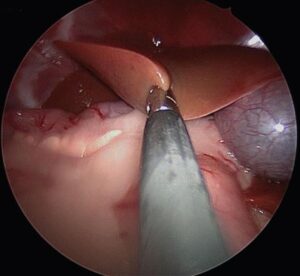

Laparoscopy is the method of choice for liver biopsy in dogs with suspected CH, as this minimally invasive method enables gross evaluation of the liver, extra-hepatic biliary system, and safe acquisition of large targeted biopsies from multiple liver lobes (Pic. 1.). A minimum of 5 biopsies from at least 2 liver lobes should be obtained for histopathology (3), aerobic/anaerobic culture (1) and quantitative copper analysis (1). Ultrasound-guided hepatic biopsy is least invasive, but small sample size frequently compromises diagnosis.

Pic. 1. Laparoscopic liver biopsy in a 2-year-old MC Havanese (McDevitt: Short-term clinical outcome of laparoscopic liver biopsy in dogs: 106 cases; JAVMA 248, No.I, January 2016)